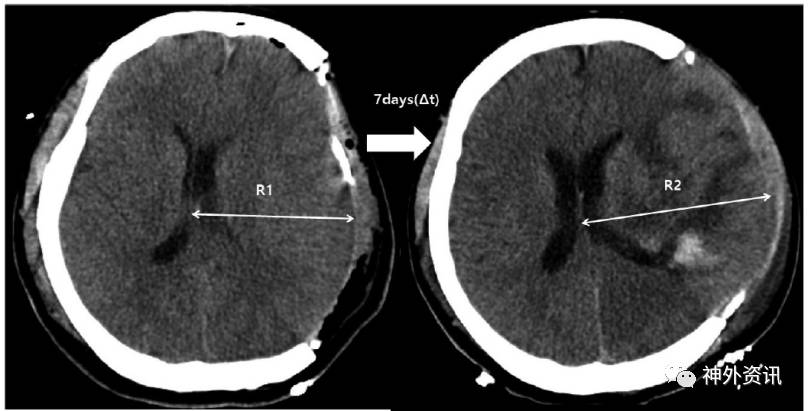

图3. 脑水肿进展速度计算公式(R2-R1)/t。